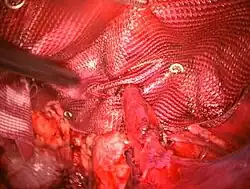

Three primary methods can be utilized: open surgery, laparoscopy, or robotic techniques. Fixing an inguinal hernia using laparoscopy causes less pain, speeds up recovery, and shows similar low rates of the hernia coming back compared to the traditional open repair method. However, open surgery can be done sometimes without general anesthesia. Using local anesthesia for open groin hernia repair, particularly in patients with additional health issues, leads to fewer complications and reduced costs.[36] Studies show that compared to regional or general anesthesia, local anesthesia results in less postoperative pain, shorter recovery times, and decreased unplanned overnight stays.[37] However, it might not be enough for repairing large hernias or in patients with abdominal domain loss, where general anesthesia is preferred.

Robot-assisted hernia surgery has also recently gained popularity as safe alternatives to open surgery. Robotic surgery for inguinal hernia repair shows outcomes comparable to laparoscopic surgery. The rates of overall complications, long-lasting postoperative pain, urinary retention, and 30-day re-admission are very similar between these two methods.[40] Just like in other areas of general surgery, it has been noted that robotic surgery for inguinal hernia repair takes more time in the operating room compared to the laparoscopic approach.[40]

Muscle reinforcement techniques often involve synthetic materials (a mesh prosthesis).[41] The mesh is placed either over the defect (anterior repair) or under the defect (posterior repair). At times staples are used to keep the mesh in place. These mesh repair methods are often called "tension free" repairs because, unlike some suture methods (e.g., Shouldice), muscle is not pulled together under tension. However, this widely used terminology is misleading, as there are many tension-free suture methods that do not use mesh (e.g., Desarda, Guarnieri, Lipton-Estrin, etc.).